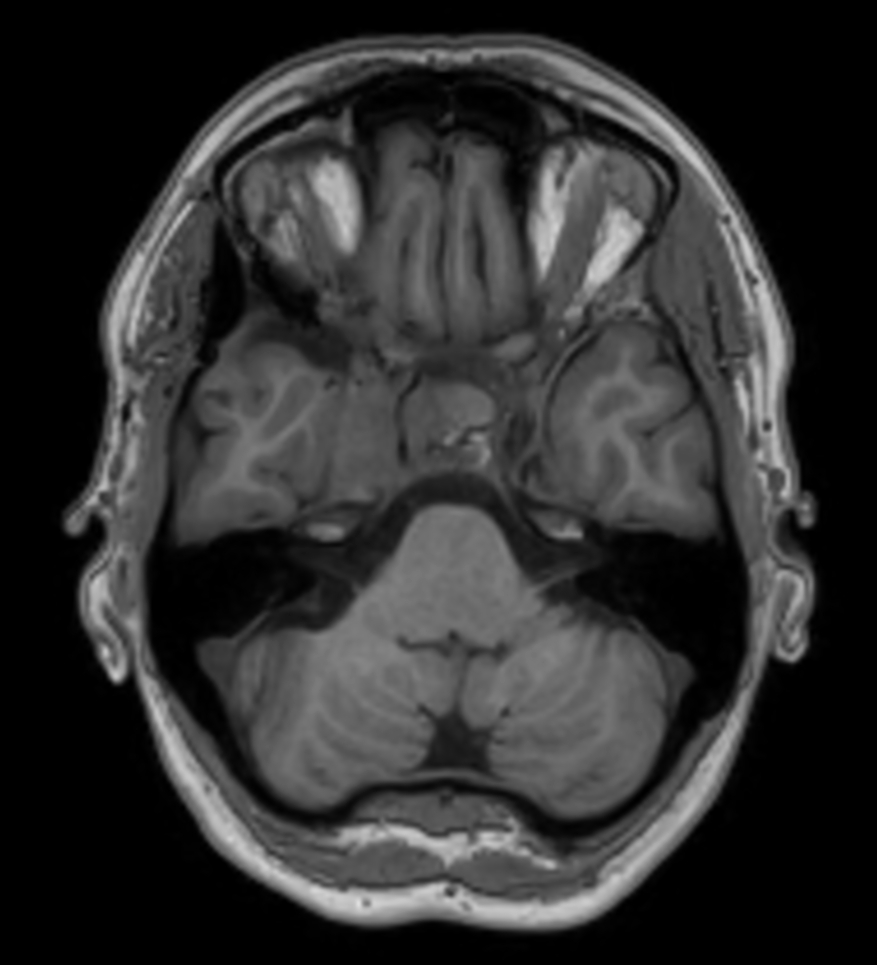

Young female referred for stereotactic treatment underwent MRI simulation.  Flex L Coils in combination with integrated FlexCoverage Posterior coil were used to image the patient in the stereotactic mask in Ingenia MR-RT 1.5T.

Axial 3D T1w TFE post contrast